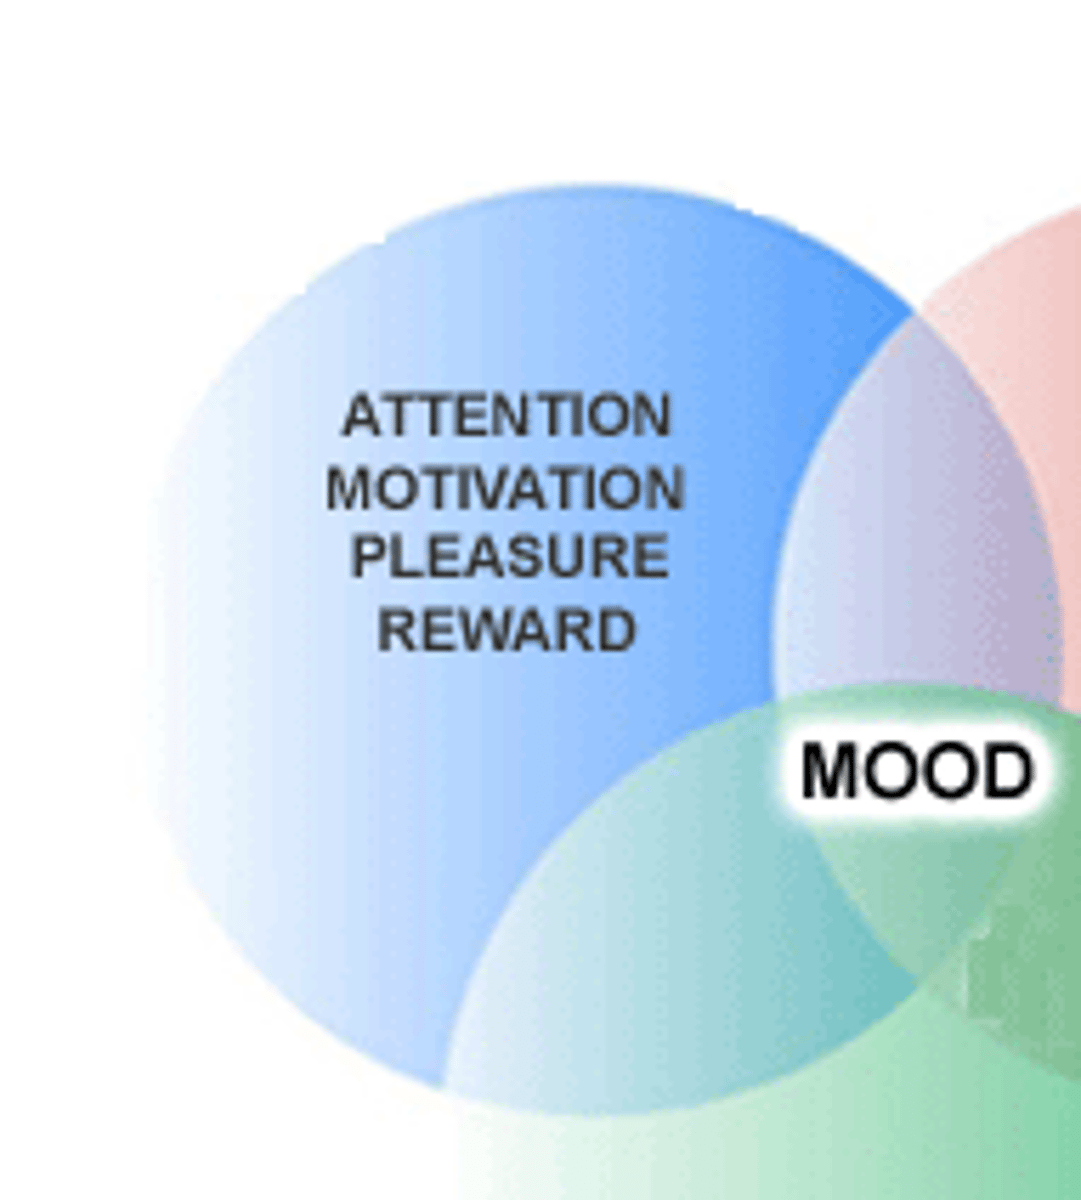

Dopamine

neurotransmitter involved in motor function, pleasure, satisfaction, and motivation

Endorphins

natural, opiate-like neurotransmitters that help manage pain, pleasure, stress, mood

neurotransmitter released by motor neurons to activate muscles; plays a role in arousal, attention, memory, and motivation

Norepinephrine (NE)

neurotransmitter that regulates brain arousal and other functions like mood, memory, hunger, and sleep

Serotonin

a neurotransmitter related to things such as mood, sleep, temperature regulation, memory, pain, and sexual activity